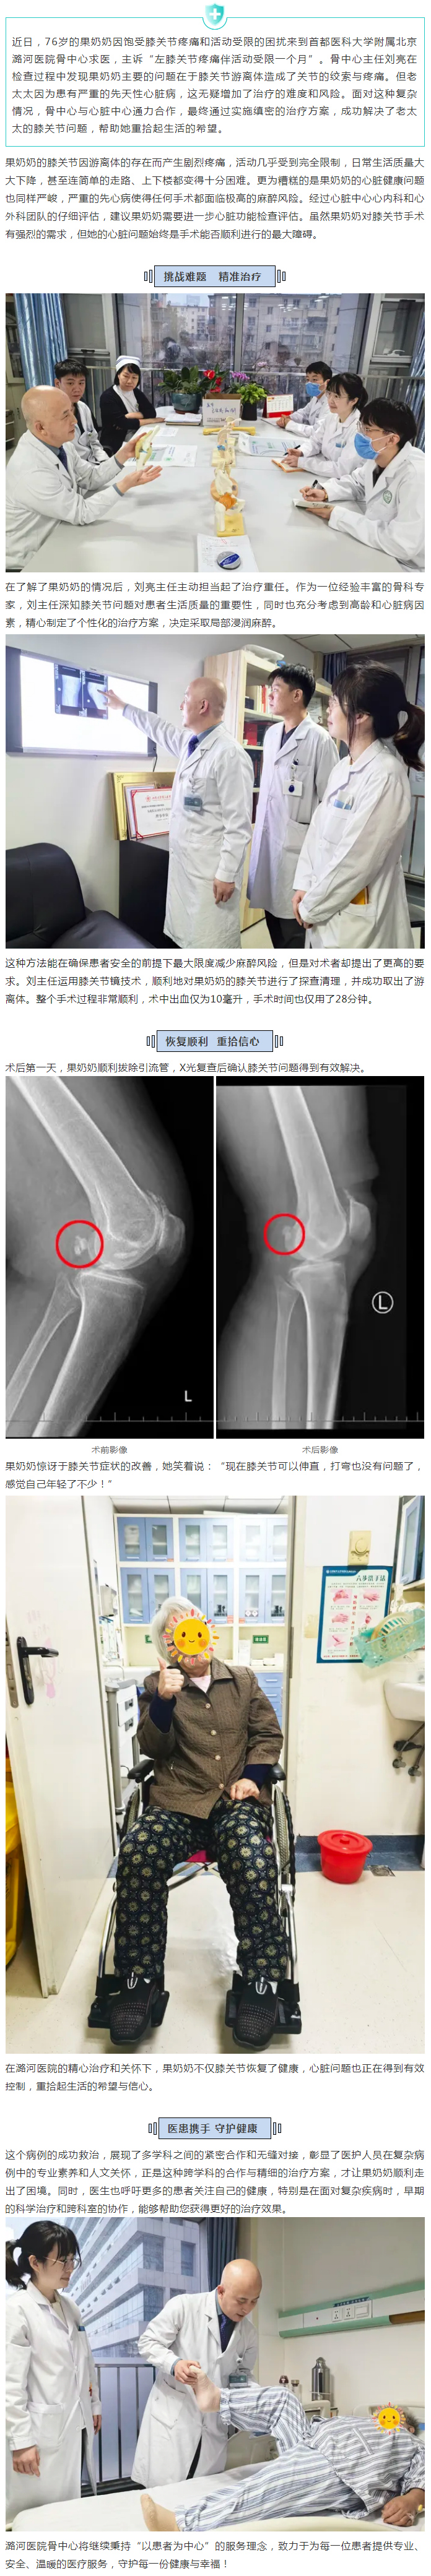

医院动态

图片新闻